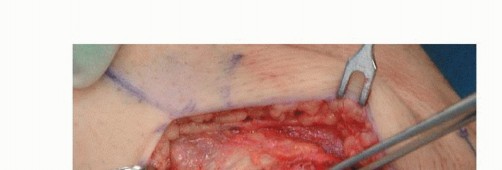

Using the standard medial approach, the distal end of the MCL often can be identified (TECH FIG 5A).

This attachment can be used in the reconstruction if the length is adequate; if not, it can be sutured to the reconstruction.

The allograft is then fixed femorally (as described earlier) and routed along the course of the superficial MCL (TECH FIG 5B).

The posterior and anterior portions of the superficial MCL can then be individually attached to the tibia.

- TECH FIG 5 • A. Medial incision. The chronically disrupted MCL stump can be visualized through the sartorius fascia. B. An Achilles tendon allograft has been sized to fit in a bone trough at the epicondylar origin of the MCL (depth gauge shown in preparation for screw fixation of the bone block). The allograft has been routed along the course of the MCL and fans out to provide the posterior and anterior portion of the MCL. (Courtesy of Mark D. Miller, MD.)